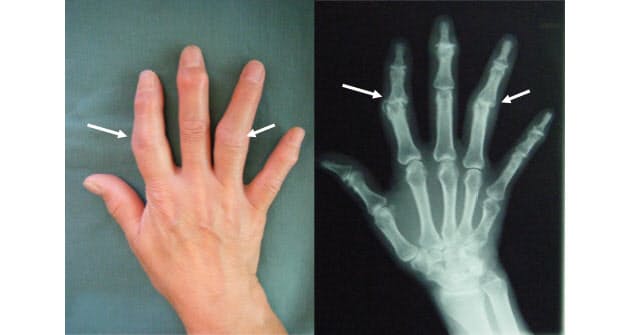

指を曲げると痛い病気 変形性関節症と関節リウマチの症状と見分け方 Nhk健康チャンネル